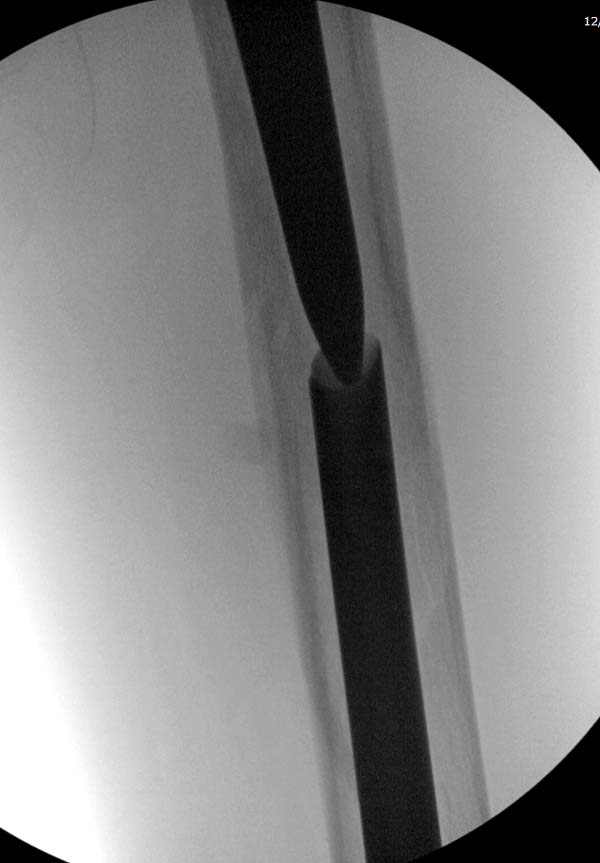

Гвоздь из ретроградного гвоздя DePuy в 15 мм получился немного тоньше,

чем у Российских коллег.

Операция не обошлась без казуса, при подготовке гвоздя произошла ошибка

в расчете. Пришлось коррегигировать по ходу операции, где длинный

дистальный отдел гвоздя срезали во время операции.